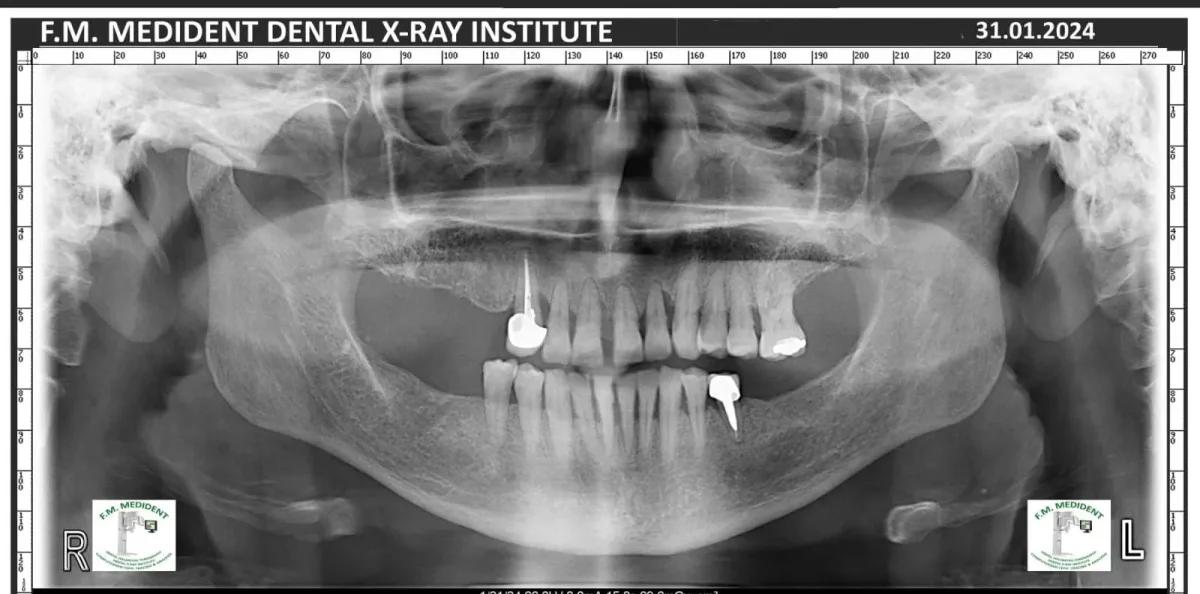

Cazuri reale înainte și după, din tratamente realizate în clinică.

Înainte

După